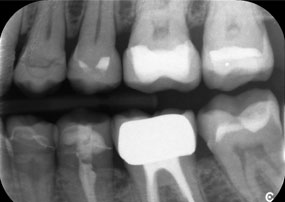

A jaw x-ray from an 81-year-old patient, in front of a black background.

Figure 1: Aesthetic rehabilitation of PFM crowns: Complete removal and replacement of 40-year-old PFM crowns to improve aesthetics in an 81-year-old patient.

Dr Wolfgang Tautschnig, a dentist with extensive experience from Salzburg, has applied and assessed the Synea Power Edition over several months in a range of clinical scenarios, particularly in the removal of zirconia crowns and the processing of base metal alloys. In one specific case, an 81-year-old patient presented seeking aesthetic improvement of her 40-year-old PFM (porcelain-fused-to-metal) crowns. The existing restorations no longer met her expectations in terms of appearance.

The challenge was to remove twelve splinted crowns made of a base metal alloy without damaging the underlying abutment teeth. The handpiece was used to precisely section the ceramic layers and divide the metal framework using a carbide bur, enabling minimally traumatic crown removal. Within just 30 minutes, the old restorations were removed, allowing for the preparation of a new prosthesis, comprising full-contour zirconia in the posterior region and veneered crowns anteriorly. The result was a complete restoration that delivered both functional and aesthetic success (see Fig. 1).